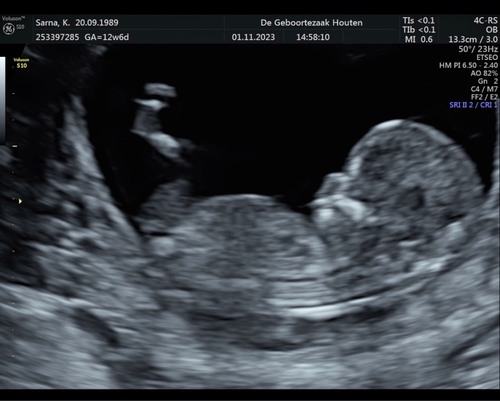

13+5 馃グ wat denken jullie

13 weken en 5 dagen 馃グ Absoluut geen idee of de nub hierop te zien is.. heb ook geen andere foto鈥檚 alleen nog 1 waar alleen het hoofdje op staat.